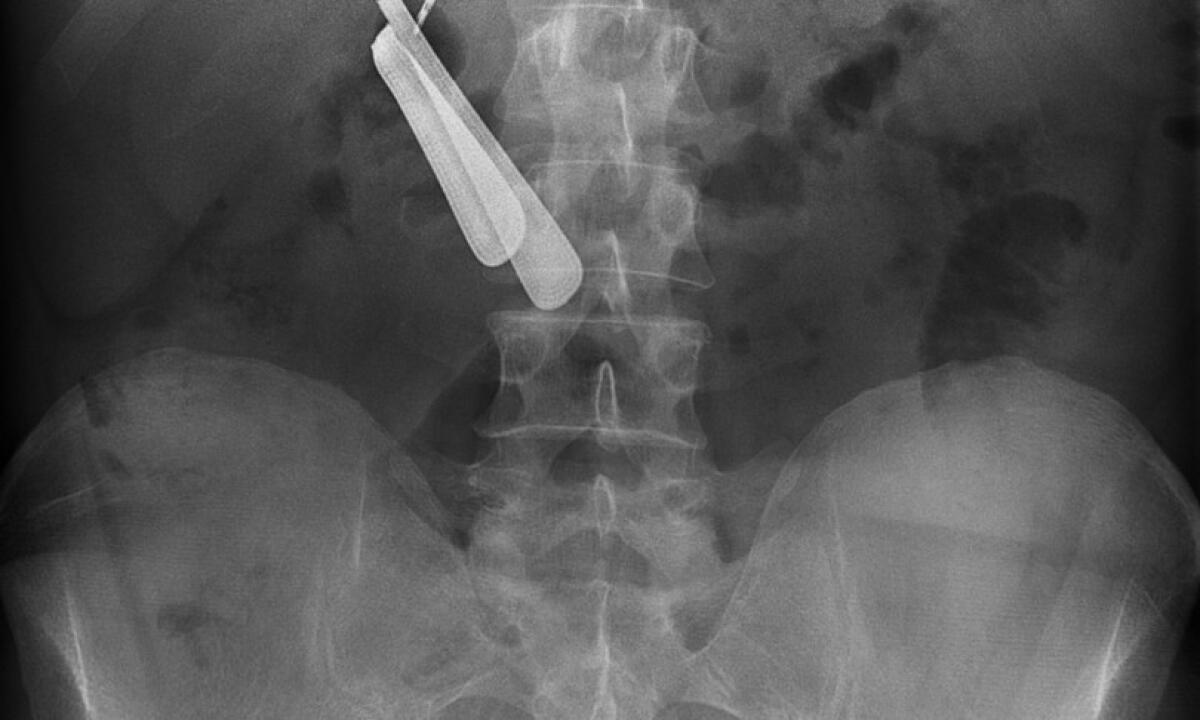

Operato d’urgenza perché nello stomaco aveva una “ferramenta”: spille, batterie, punte di trapano, brugole, accendini, pezzi di vetro, dadi, viti e una forchetta. Tutto visibile grazie ad una radiografia. È stato così che un uomo di mezza età è stato sottoposto ad un intervento chirurgico presso l’Icot di Latina. Il paziente è arrivato al pronto soccorso lamentando solo spossatezza, poi i medici hanno gestito al meglio il tutto.

“L’intervento è riuscito, il paziente sta bene ed è stato già dimesso”, ha spiegato al quotidiano il Messaggero, il professor Giuseppe Cavallaro, responsabile dell’Unità operativa di chirurgia generale a gestione universitaria dell’Icot. “Non sappiamo come sia stato possibile ingerire tutti quegli oggetti e non avere conseguenze - spiega Cavallaro - anche per noi è stato un caso limite, probabilmente il primo di questa portata a livello nazionale”.

È probabile che tutti gli oggetti siano stati ingeriti negli ultimi mesi. Da una prima diagnosi potrebbe essersi trattato di

un caso di “picacismo”, un disturbo di origine psichiatrica che porta a ingerire frequentemente (per almeno un mese) oggetti e sostanze non commestibili anche se la vicenda non è ancora stata chiarita.